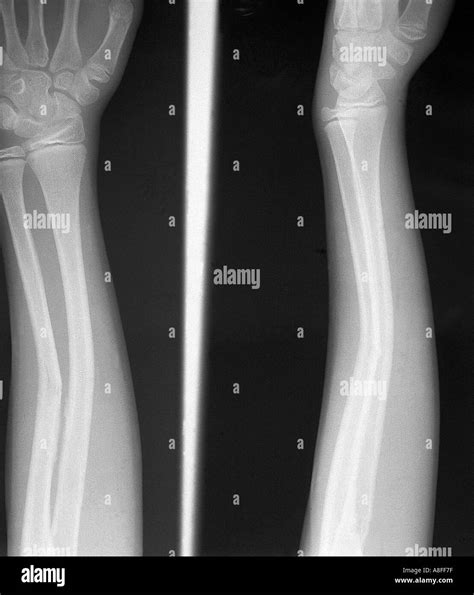

Diagnosing a fractured radius ulna involves a combination of physical examination and imaging tests. The diagnostic process typically includes:

• X-Rays: X-rays are the primary imaging tool used to confirm the presence and severity of a fracture. They provide detailed images of the bones and can show the exact location and type of fracture.

• CT Scans or MRI: In some cases, a CT scan or MRI may be ordered to provide more detailed images, especially if the fracture is complex or if there is concern about soft tissue damage.